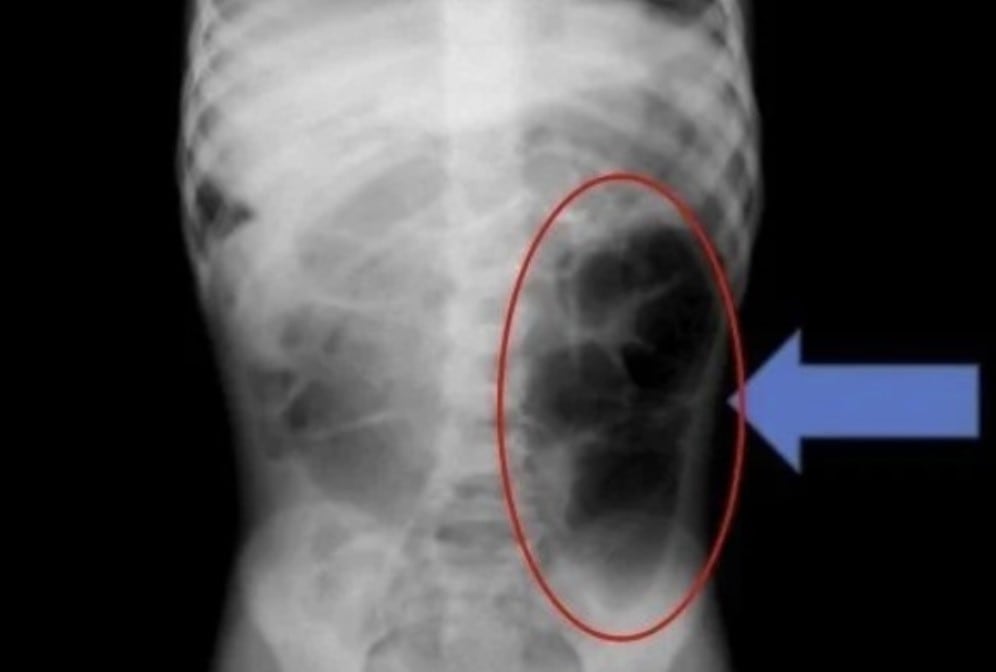

복통 호소한 6세 여아, 뱃속 가득 찬 건 ‘머리카락 뭉치’였다